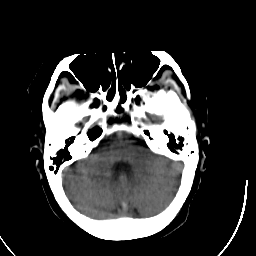

Stroke CT #3 -- Slice #5

[Home][Help][Clinical] Slice 5